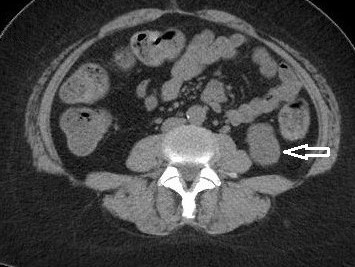

Los síntomas generalmente son inespecíficos (dolor abdominal, fiebre, dispepsia), dependen de la extensión del trombo y del momento evolutivo. En el laboratorio se puede observar aumento de los reactantes de fase aguda, y en algunos casos, elevación leve de las transaminasas. El diagnóstico se realiza mediante estudios de imagen, como la Ecografía Doppler, TC y RM, con el fin de descartar otras causas, ya que muchas veces es un hallazgo incidental. El Gold Estándar es la TC con contraste EV.

En este caso, presentamos una paciente femenina de 43 años de edad con antecedente de uso de ACO, a quien se le diagnosticó Trombosis portal mediante TC de abdomen c/cte. EV y trombofilia con mutación en el factor II de protrombina 20210, con evolución favorable.

Paciente femenina de 43 años, antecedente de obesidad grado I. Medicación habitual uso de ACO. Antecedente quirúrgico: una cesárea. Presenta cuadro clínico caracterizado por epigastralgia súbita de moderada intensidad. Se automedica con Buscapina sin mejoría del cuadro, por lo que acude a guardia. Le realizan TC y la derivan con diagnóstico de trombosis portal de la rama izquierda.

Se solicita nueva tomografía para descartar progresión de la trombosis y se vuelve a instaurar analgesia y anticoagulación EV.

Hallazgos imagenológicos

El diagnóstico se realiza mediante ecografía (Modo B y Doppler) y se confirma la extensión y la presencia de factores asociados mediante TC con CTE y RM con CTE EV.

El Gold Estándar es la TC con contraste EV.